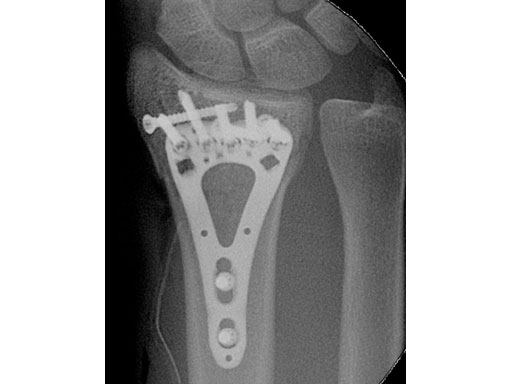

Fig 3ac Postoperative x-rays showing comparison of plate alternatives.